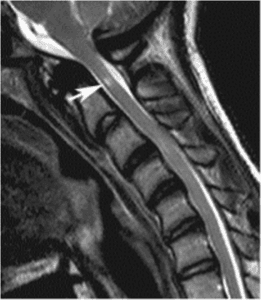

In infants affected by achondroplasia, there is frequently a constriction at the base of the skull known as the foramen magnum. This narrowing can impede the passage of the brainstem and spinal cord. This compression can result in muscle weakness and respiratory difficulties. In rare cases, it can be life-threatening.

To assess the size of the foramen magnum, your child’s doctor may request an MRI scan of the spine. If deemed necessary, you may be referred to a neurosurgeon for a decompression surgery aimed at enlarging the opening in the skull to alleviate spinal cord compression